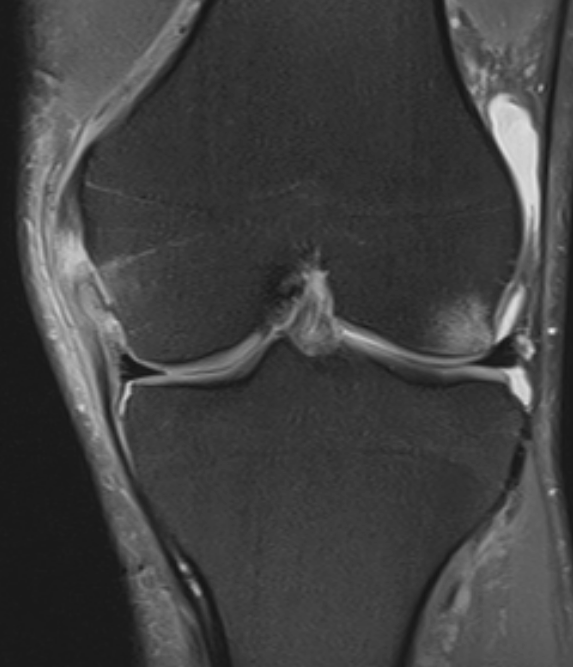

3. Medial Collateral Ligament Injury (Grade 2)